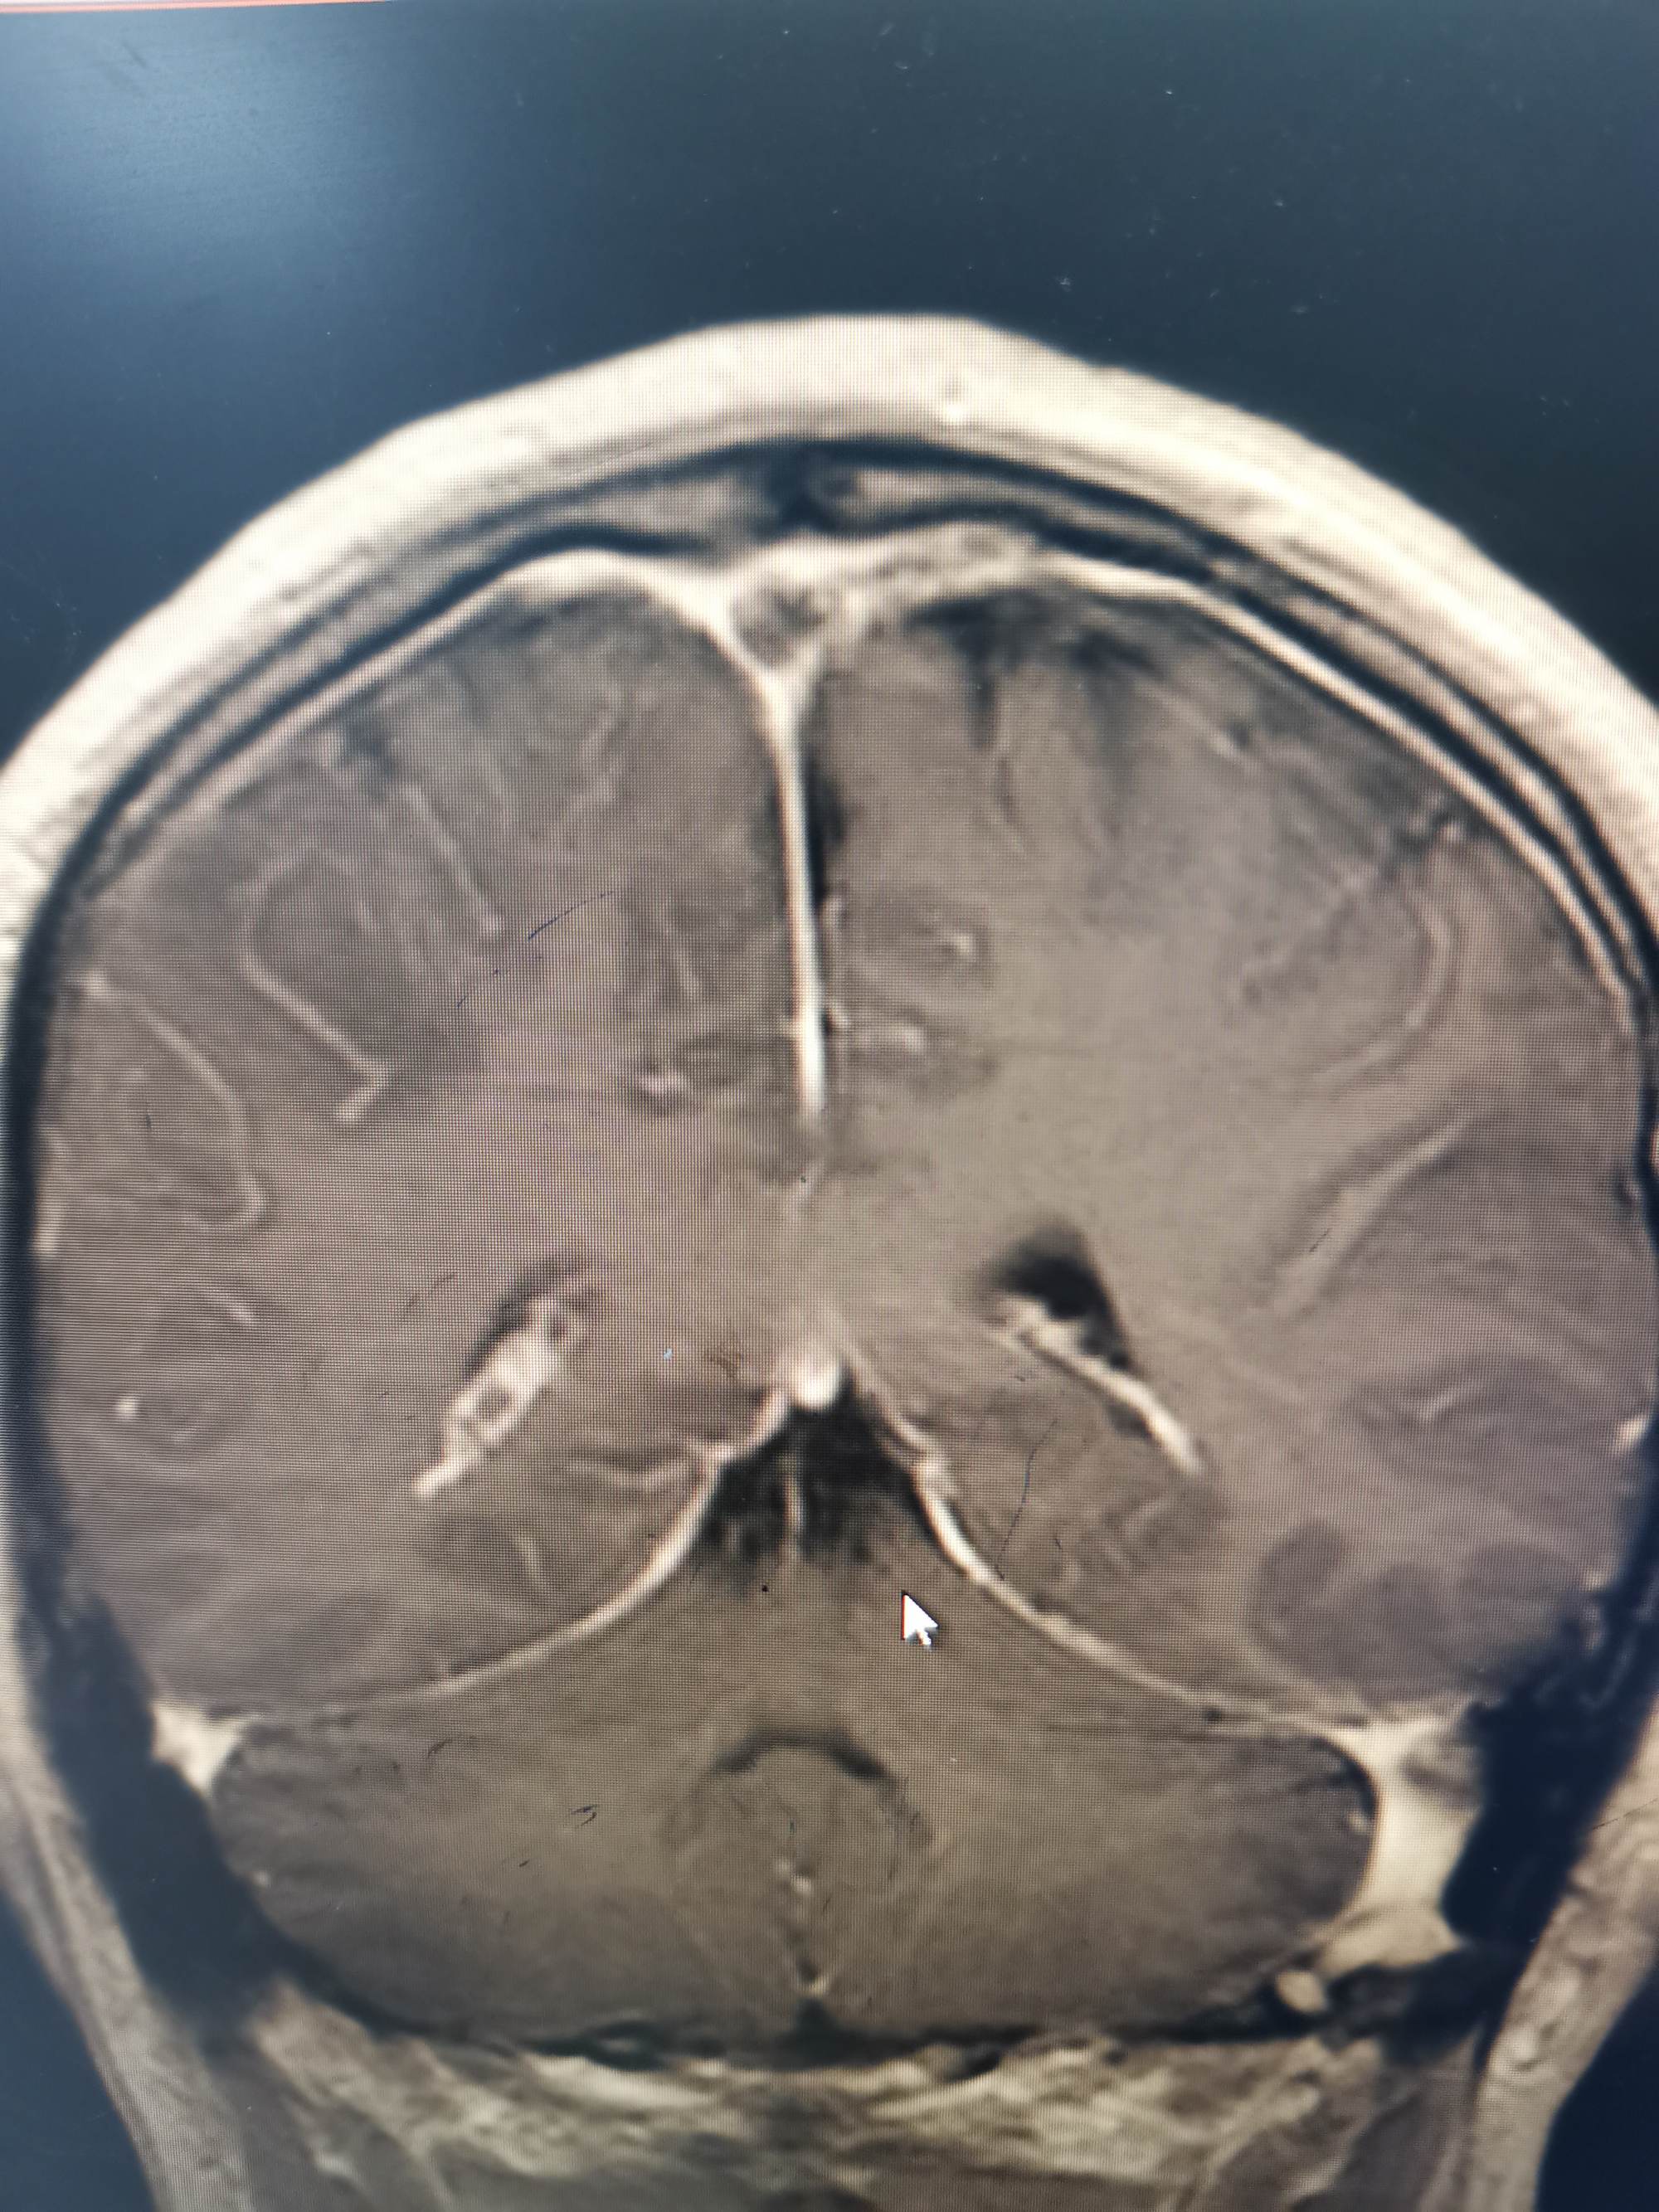

外院磁共振提示右侧顶叶病变

入院后急查头颅磁共振发现顶叶又新发两个病灶。

磁共振发现顶叶又新发两个病灶

DWI考虑新发病灶为脑梗死,考虑该梗塞病灶位于运动皮层导致患者右下肢完全偏瘫。

磁敏感成像考虑首发病灶为出血。

增强显示矢状窦长节段充盈缺损,D-2聚体大于正常上限5倍以上。我科诊断考虑上矢状窦血栓形成伴多发多次脑梗死伴出血。